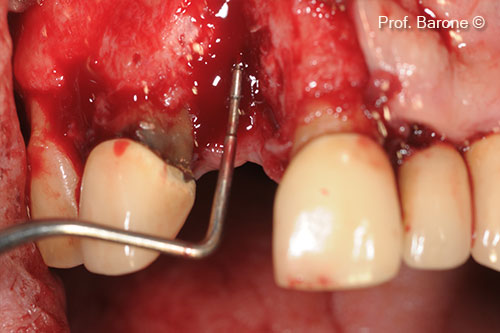

Hình thái khuyết hổng xương có sự khác biệt giữa các bệnh nhân. GTO® là vật liệu ghép dị loại dạng Sticky bone hai pha (Dual-Phase), được đặc trưng bởi khả năng thích ứng cao với vị trí tiếp nhận và độ ổn định vượt trội sau khi ghép. GTO® cho phép hình thành xương mới đầy đủ⁽¹–⁴⁾ và bảo tồn thể tích ổ răng khi được sử dụng trong GBR⁽⁵⁾ tại các ổ răng sau nhổ có kế hoạch cấy ghép trì hoãn, kể cả trong những trường hợp ổ răng sau nhổ bị tổn thương. Khi kết hợp với Lamina® , GTO® cũng là lựa chọn phù hợp trong điều trị các khuyết xương theo chiều ngang⁽¹⁾ (ví dụ: mào xương dạng lưỡi dao – knife-edge ridge).Nhờ tính bám dính và khả năng thao tác dễ dàng, GTO® có thể được sử dụng để tái tạo xương quanh các khiếm khuyết dạng hở quanh implant (peri-implant dehiscence)⁽⁵⁾ .